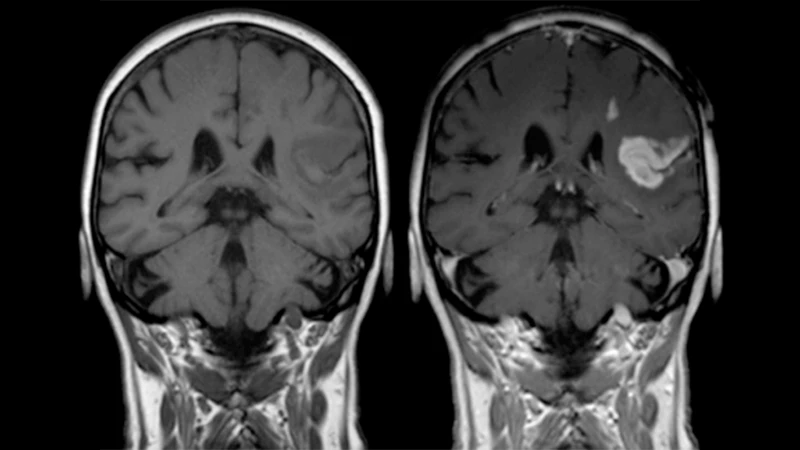

2. To Characterize Tumors and Masses

Many tumors, both cancerous and benign, develop their own unique blood supply. How a mass "enhances"—or lights up—after contrast injection gives the radiologist important clues about what it might be. Some patterns of enhancement are characteristic of specific types of tumors, helping to guide the diagnosis.